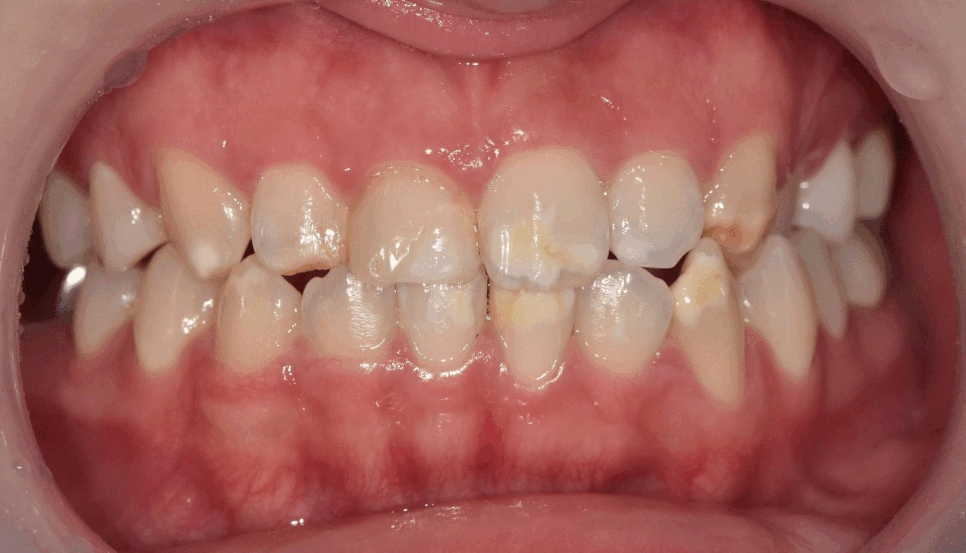

이 환자분은 하얀 반점 때문에

마음대로 웃지도 못한다고 하셨어요.

입안을 보니, 하얀 반점이 치아의 절반 이상을 덮을 만큼 퍼져 있습니다.

치아 절반 이상을 덮은 하얀 반점

특히 왼쪽 송곳니는 탈회가 진행돼서 초기 충치로 변하고 있는 상태였어요.